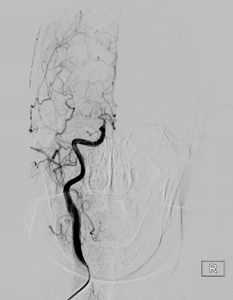

流行病学研究基本上将脑卒中分为出血性卒中和缺血性卒中两大类。出血性脑血管病包括:颅内动脉瘤、脑血管畸形、高血压脑出血等。

缺血性脑血管病包括各种病因如颅内动脉狭窄、颈动脉狭窄、椎动脉狭窄、锁骨下动脉狭窄、烟雾病(Moyamoya病)、动脉粥样硬化疾病或心源性疾病导致的脑缺血。在我国急性缺血性脑卒中是最常见的卒中类型,约占脑卒中的69.6%~70.8%,在空间分布上有北方高、南方低的趋势,这与高血压患病率的空间分布几乎一致。急性缺血性脑卒中的处理包括早期诊治、早期预防再发(二级预防)和早期康复。随着医疗技术水平的提升及医学材料科学的进步,缺血性卒中的治疗由早期的静脉药物溶栓治疗发展为血管内溶栓、急诊支架取栓等多种治疗方式。而对于预防缺血性脑卒中事件的发生,颈动脉内膜剥脱术、脑血管搭桥手术、责任血管的球囊扩张加支架置入术等多种治疗方案亦发挥着不可替代的作用。

脑卒中的诊疗是一项系统工程,需要公立三甲医院多部门、多科室的配合协调,建立一个快捷的绿色通道,最终实现对脑卒中的有效救治。北京积水潭医院神经外科通过前期人才储备、交流学习,目前已建立了脑血管病的介入诊疗及多种外科手术治疗的整体治疗方案,同步开通了脑血管病筛查门诊和缺血性脑血管病专病门诊,并已开展了相应的手术,更好地服务于患者。